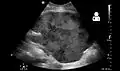

Imaging

Post operatively, kidneys are periodically assessed by ultrasound to assess for the imaging and physiologic changes that accompany transplant rejection. Imaging also allows evaluation of supportive structures such as the anastomosed transplant artery, vein, and ureter, to ensure they are stable in appearance.

The major sonographic scale in quantitative ultrasound assessment is with a multipoint assessment of the resistive index (RI), beginning at the main renal artery and vein and ending at the arcuate vessels. It is calculated as follows:

- RI = (peak systolic velocity – end diastolic velocity ) / peak systolic velocity

The normal value is ≈ 0.60, with 0.70 being the upper limits of normal.[57][58]

- Postoperative bleeding following kidney transplant as seen on ultrasound[67]

Postoperative bleeding following kidney transplant as seen on ultrasound[67]